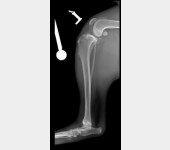

Nazywam się JJ :) Nigdy nie sądziłem, że będę potrzebował Waszej pomocy. Mam dopiero rok, urodziłem się 14 kwietnia 2019 roku. Lubię biegać, popiardywać, walczyć z odkurzaczem i dawać buziaczki człowiekom. Moi kochani opiekunowie przygarnęli takiego klopsa jakim jestem (a raczej byłem) ja... Mając zaledwie 4 miesiące zachorowałem na parwowirozę. Moje człowieki zrobili i oddali wszystko co mogli dać, abym wyzdrowiał. I tak się stało! Jednak zacząłem chorować bardzo szybko i po cichutku. Zaczęły boleć mnie moje tylnie nogi. Starałem się biegać, ale moje kolanka za bardzo bolały, więc ograniczyłem używania tylnich nóg do minimum podczas biegania. Żeby wejść na kanapę muszę bardzo się wysilić lub prosić moich człowieków, aby mi pomogli. Nie jestem w stanie wejść ani zejść po schodach bez odpoczynku. Moi kochani bracia i siostry (bo jesteśmy liczną rodzinką) patrzą na mnie z przykrością... Moje nietypowe siadanie na boku zaciekawiło domowników. Musiałem stworzyłem sobie garb, aby odciążyć nogi. Później pojawiły mi się guzki na prawej i lewej nodze. Na lewej nóżce guzek był troszkę większy, więc od razu pojechaliśmy do weterynarza. Niedobrze, bo guzki były już troszkę duże... Zapalenie, a może początek raka. Moja nowa Pani weterynarz zaczęła podejrzewać dysplazję biodrową. To mogłoby wyjaśnić moje “dziwaczne” siedzenie. Jednak nie była pewna, więc wysłała nas do specjalistów. Tam zrobili mi zdjęcia rentgenowskie i trochę mnie powyciągali. Bardzo mnie to bolało. Czułem wszystko, pomimo Jasia, którego dostałem. WERDYKT: Ześlizg główek w kościach kolana lewego i prawego o 33%, a to podobno bardzo dużo. Moje guzki to skutek rozlanego płynu zapalnego w kolanach. Moje lewe kolano choruje bardziej niż prawe. Jak się okazało nie urodziłem się z tym, ani nie jest to genetyczne. Po prostu zachorowałem na to. Moje kochane człowieki dostały dwie opcje.